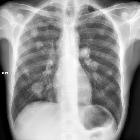

Cannonball metastases refer to multiple large, well-circumscribed, round pulmonary metastases that appear not unsurprisingly like cannonballs. The French terms "envolée de ballons" and "lâcher de ballons", which translate to "balloons release", are also used to describe this same appearance.

Metastases with such an appearance are classically secondary to :